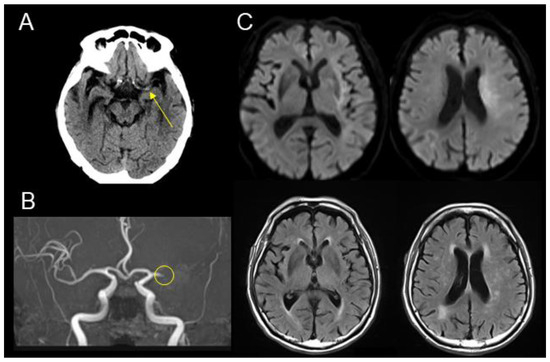

2. Case Presentation